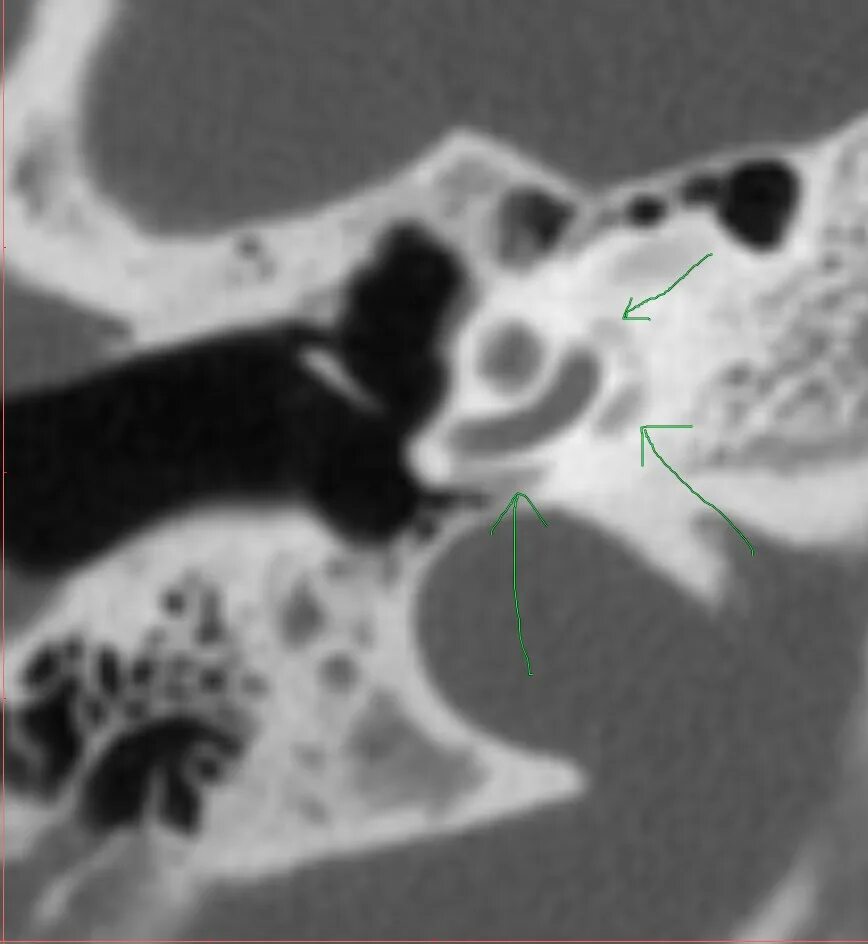

Кохлеарный отосклероз